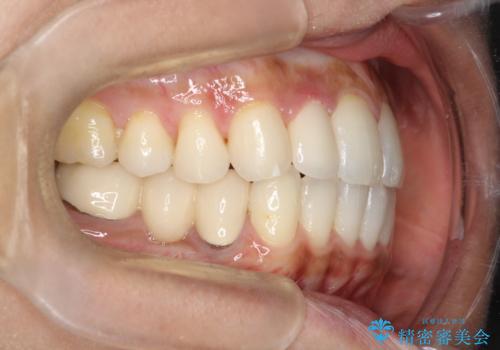

【インビザライン】矮小歯を有する方の矯正治療

- 前歯の凸凹を主訴に来院されました。

元々、歯が小さかったため矯正終了後にセラミックにて修復治療を行う治療計画をたてインビザラインにて治療を行いました。

今回はスペースを作るために歯列の拡大をメインでおこなっています。